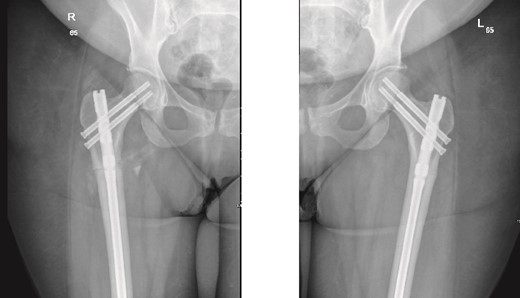

The patient was seen in the clinic at 2 weeks, 6 weeks, and 6 months post-surgery. She was doing well, reporting only mild pain. She was fully weight-bearing with the assistance of a cane and had good range of motion (Figs 3 and 4).

6-weeks follow-up anteroposterior (AP) view of the right and left femurs after CRIF with IM nail.